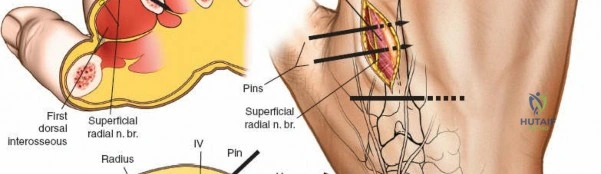

* Middle Third: Pins can be placed dorsolaterally. The superficial radial nerve (SRN) and cephalic vein must be protected.

* Distal Third: The SRN emerges from beneath the brachioradialis approximately 9 cm proximal to the radial styloid. Pins are typically placed at a 45-degree angle between the extensor carpi radialis longus (ECRL) and brachioradialis, or directly laterally. A mini-open approach is critical here.

Distal Radius Pin Placement

1. Identify the interval between the brachioradialis and the ECRL.

2. Make a 2-3 cm longitudinal incision.

3. Carefully identify and retract the superficial radial nerve branches.

4. Place the drill sleeve directly on the radial styloid or slightly proximal, aiming ulnarward and slightly dorsally.

5. Insert 3.0 mm or 4.0 mm pins.

2. Dissect bluntly, protecting the dorsal sensory branches of the radial nerve and the extensor tendons.

2. Dissect bluntly to avoid the SRN.

Neurovascular complications, while less common, carry significant morbidity. The radial nerve is at highest risk during humeral fixation, while the superficial radial nerve is frequently irritated or injured during distal radius fixation. Adherence to the mini-open technique, utilizing blunt dissection to the periosteum, is the standard of care to mitigate this risk.